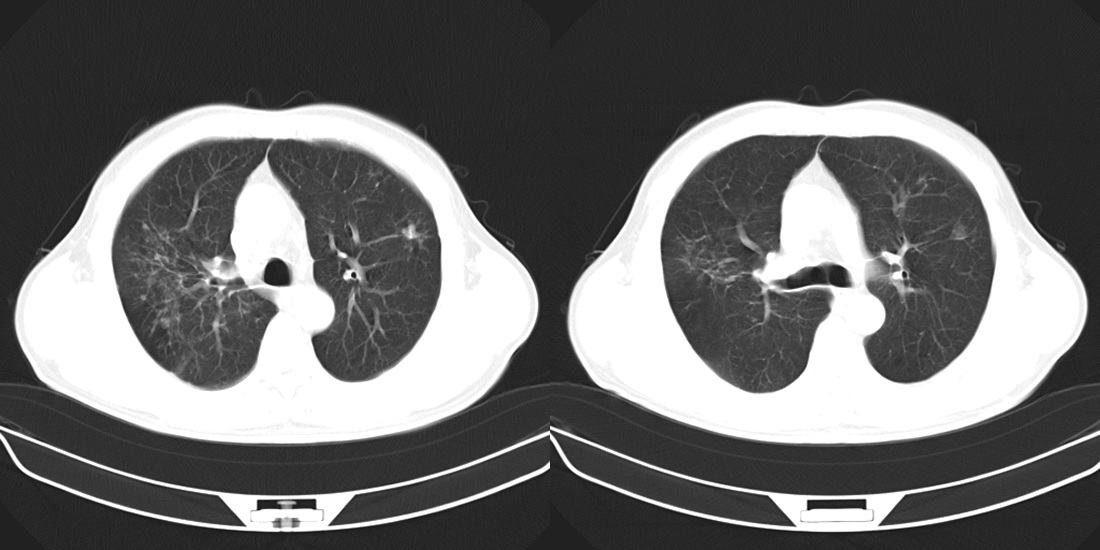

标题: CT10251:男性56岁,结核球? [打印本页]

标题: CT10251:男性56岁,结核球?

56岁男性,低热、消瘦,曾x线诊断肺结核。

两肺结核,左肺结核球。

双肺结核伴左上肺结核球形成

两肺多形性病变,支持肺结核.

两肺多形性病变,且在结核好发部位。支持肺结核.